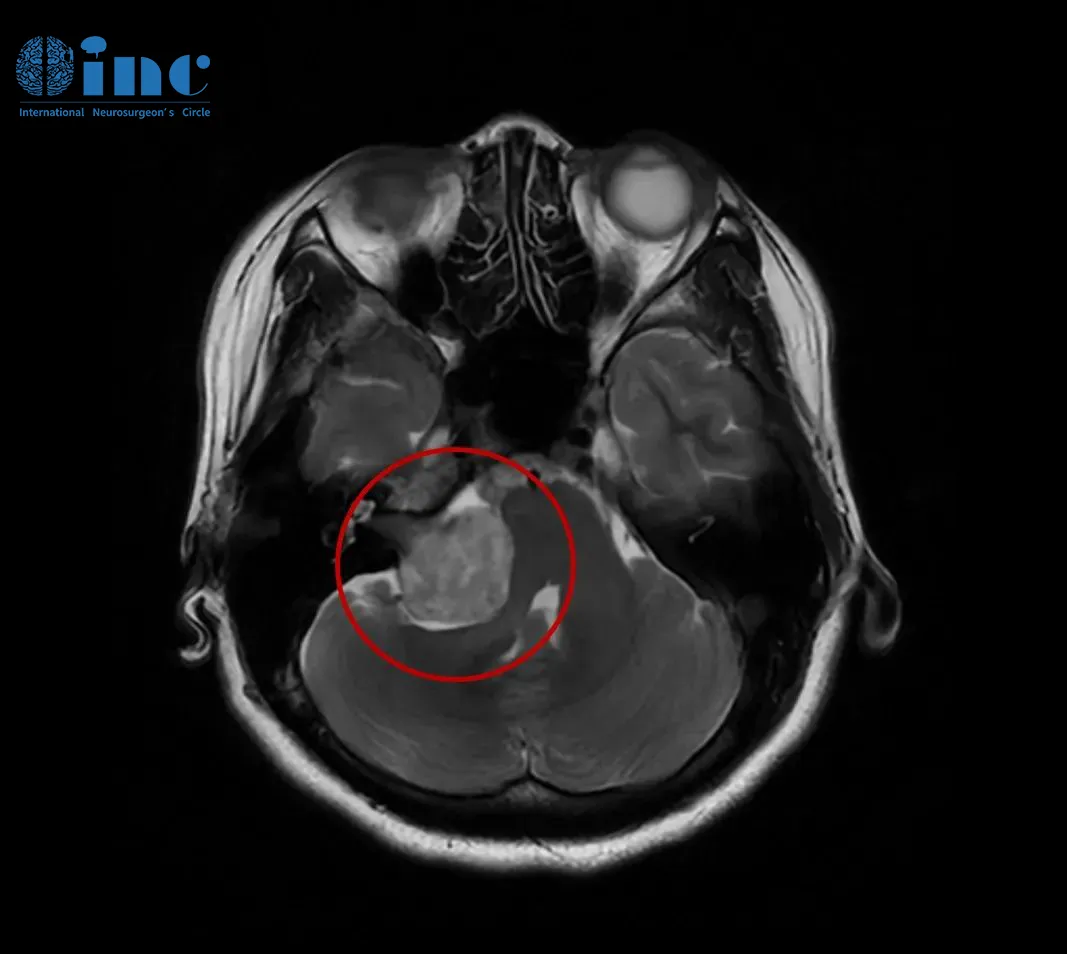

明明感觉身体不适,可就是查不出原因,各种症状持续了一年半左右的时间。到了2021年末,李女士发现自己不仅右侧耳闷、听力下降,右眼视力轻微下降,右侧舌部和面部麻木加重,还伴有轻微站立不稳的症状,甚至右侧手臂用力拿东西时出现疼痛感,例如炒菜时拿不起锅。因此,她再次到医院做了头颅核磁,发现右侧CPA区前庭神经鞘瘤,病灶最大直径约为35mm(包括内听道内的部分),脑干受压迫,桥脑及右侧桥臂受压,四脑室变形,增强扫描显示明显强化。她再次拿出2019年的CT影像问医生,那个时候为什么没有检查出病情,医生表示当时确实无法发现这个肿瘤。

INC巴教授在对李女士的病情详细分析后回复表示,她患的是一种典型的(右侧)前庭神经鞘瘤,最大直径为35毫米(包括内听道内的部分),肿瘤已经压迫脑干,有明显的手术指征,建议手术治疗。